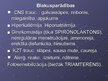

Diurētiskie līdzekļi

Diurētiskie līdzekļi

Diurētiskie līdzekļi